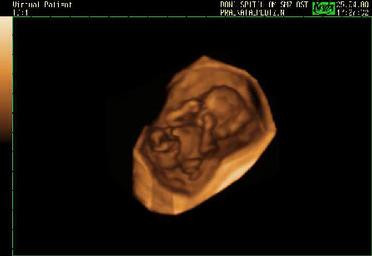

first trimester ultrasound